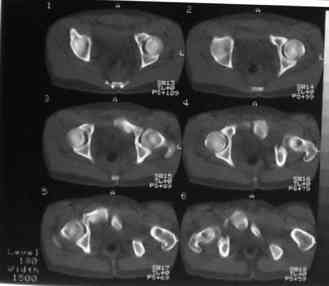

Уважаемые коллеги! На днях оперировал перелом таза месячной давности - разрыв симфиза, перелом обеих ветвей правой лонной кости, трансфораминальный перелом крестца слева. Представляю рентгенограммы с задержкой - технические причины.

Предоперационные рентген и КТ, в операционной - снимки после каждого фиксатора. Вертикальное смещение полностью устранить не удалось. В первую очередь за счет заднего полукольца. Хотя при компрессии на стержнях горизонтальное смещение было сантиметра 1,5. Т.е. крестец, на мой взгляд еще не сросся. От коллег хотел-бы услышать допустима-ли такая остаточная деформация?